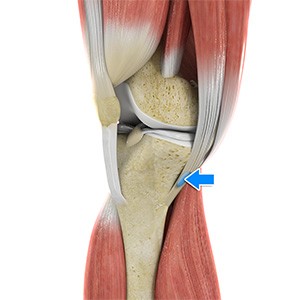

Pes Anserine Bursitis

Bursitis refers to the inflammation and swelling of a bursa. A bursa is a small fluid-filled sac found between soft tissues and bones that lubricates and acts as a cushion to decrease friction between bones when they move.